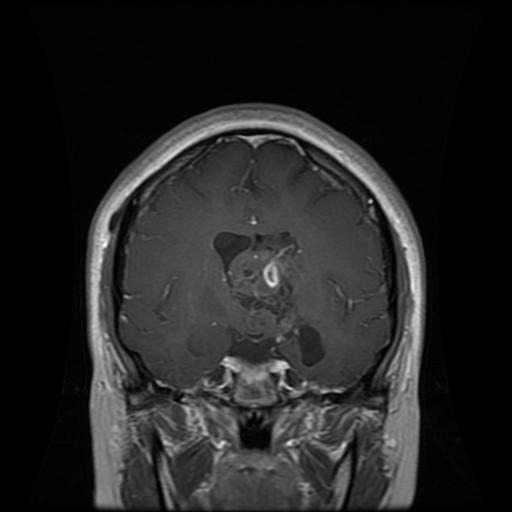

Figure 2: Samples of Meningioma segmentation across different imaging planes

Meningioma: Meningiomas arise from the meninges and are generally well‑circumscribed and homogeneous, making them easier to segment. However, their location adjacent to critical structures such as dural sinuses and cranial nerves can complicate diagnostic tasks. An example of a meningioma and its segmentation mask is presented in Figure 2, illustrating the clarity of its boundaries.